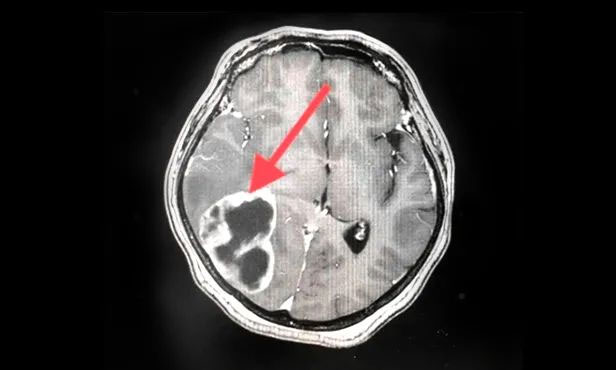

▲ 刚入院时病灶影像

▲ 完成穿刺,黑色囊液被顺利引流